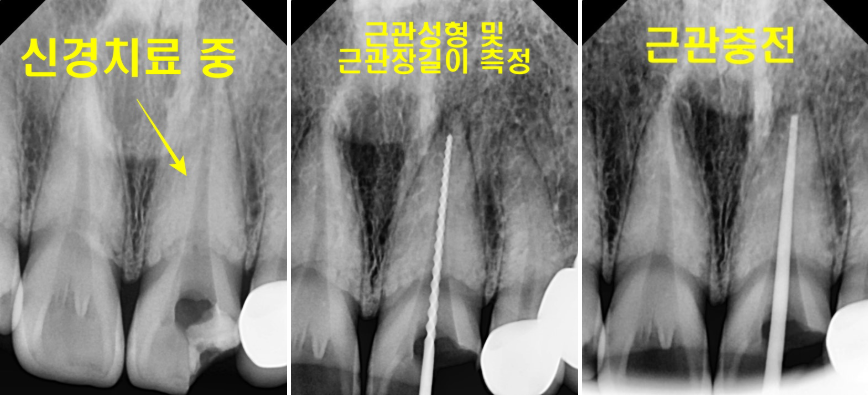

Endo를 하는 기간에,

깨끗하게 해 줘야 되기 때문에

근관장 길이를 측정 해 주고,

여러번 소독을 해 주면서

근관성형과 근관확대를 진행합니다.

하루만에 끝나는 것이 아니라,

적어도 3-4일에 한 번씩

세척과 소독을 진행해야 합니다.